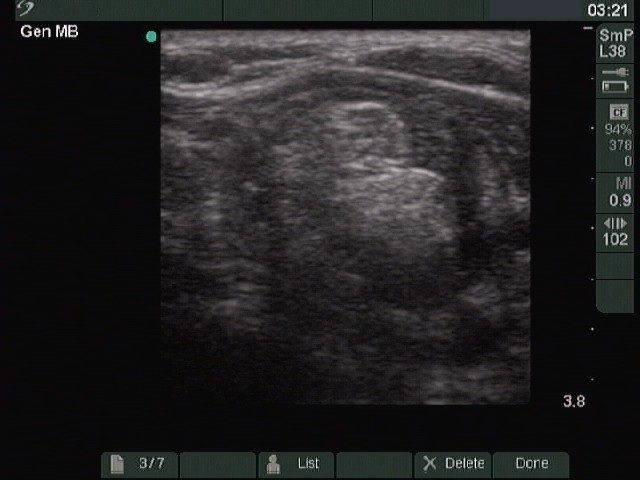

Ultrasonography. The right lobe was intact, while the left was composed of a large nodular area with multiple hypoechogenic and hyperechogenic discrete lesions. The latter corresponded to necrosis.